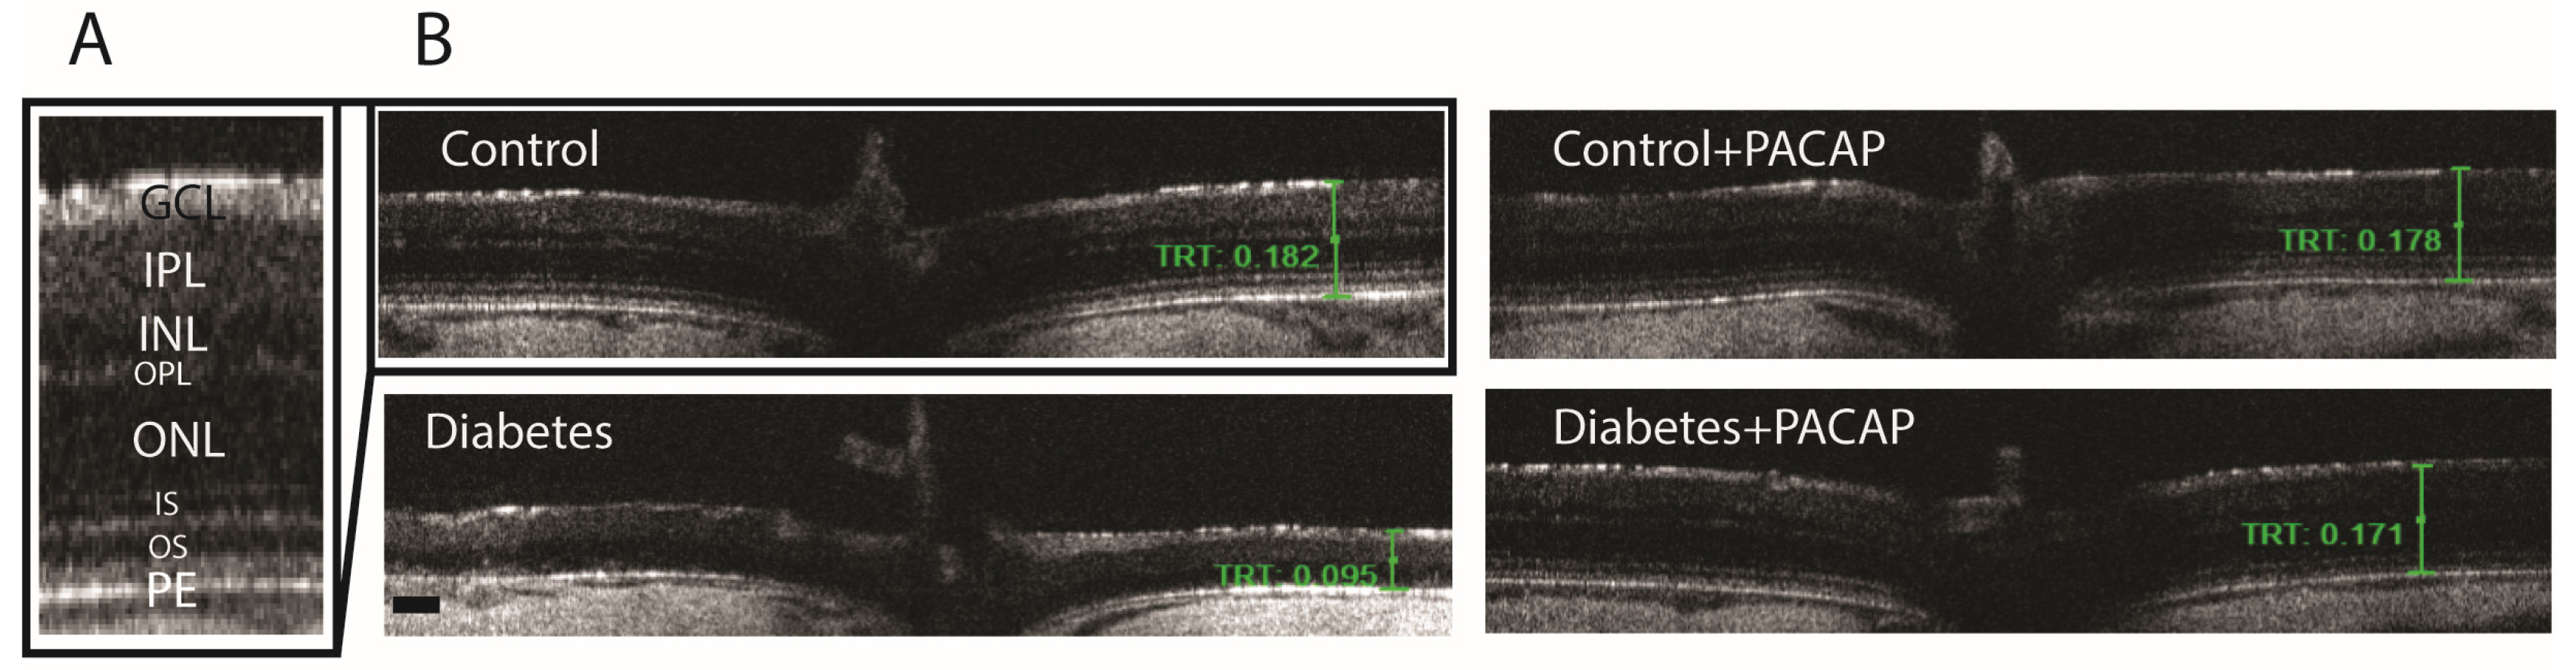

2.3. Effects of PACAP Eye Drop Treatment on Histological Changes

4.5. Electroretinography (ERG)